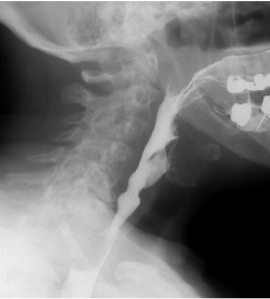

Pharynx

bolus passes through this passageway (bolus is softened food from chewing)

also known as throat

Uvula

folds back to block food from going down nose and into the laryngopharynx

Epiglottis

flap of tissue that closes opening to the larynx and trachea

Peristalsis

wave like involuntary muscle movement that helps bolus pass through pharynx and esophagus